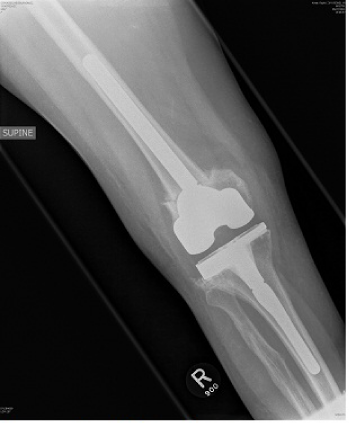

Post operatively, full ROM and full weight bearing was permitted from post-operative day two. By six week follow up the patient was fully weight bearing without any aids; radiographs demonstrated bony union at the osteotomy site with good alignment (Figure 4–6). At one year review, the patient was pain free, with a ROM of 0° to 110° without a quadriceps lag, and with clinically acceptable alignment (Figure 7). Pre and postoperative knee scores are listed in Table 1.

Figure 5 Postoperative AP view of the knee.

Figure 6 Postoperative lateral view of the knee.

In the literature to date there has not previously been a report of a simultaneous peri-articular femoral osteotomy and total knee arthroplasty for a severe arthritic valgus knee of >45°. In this patient, excellent alignment both clinical and radiological was obtained, with the valgus deformity improving from 45° to 7° of valgus. Symptomatically, at 1 year follow up the patient is doing extremely well with good ROM and is pain free, without any complications. We believe that this operative technique in severely valgus knees allows for excellent correction of malalignment, aids soft tissue balance with good patient outcome.